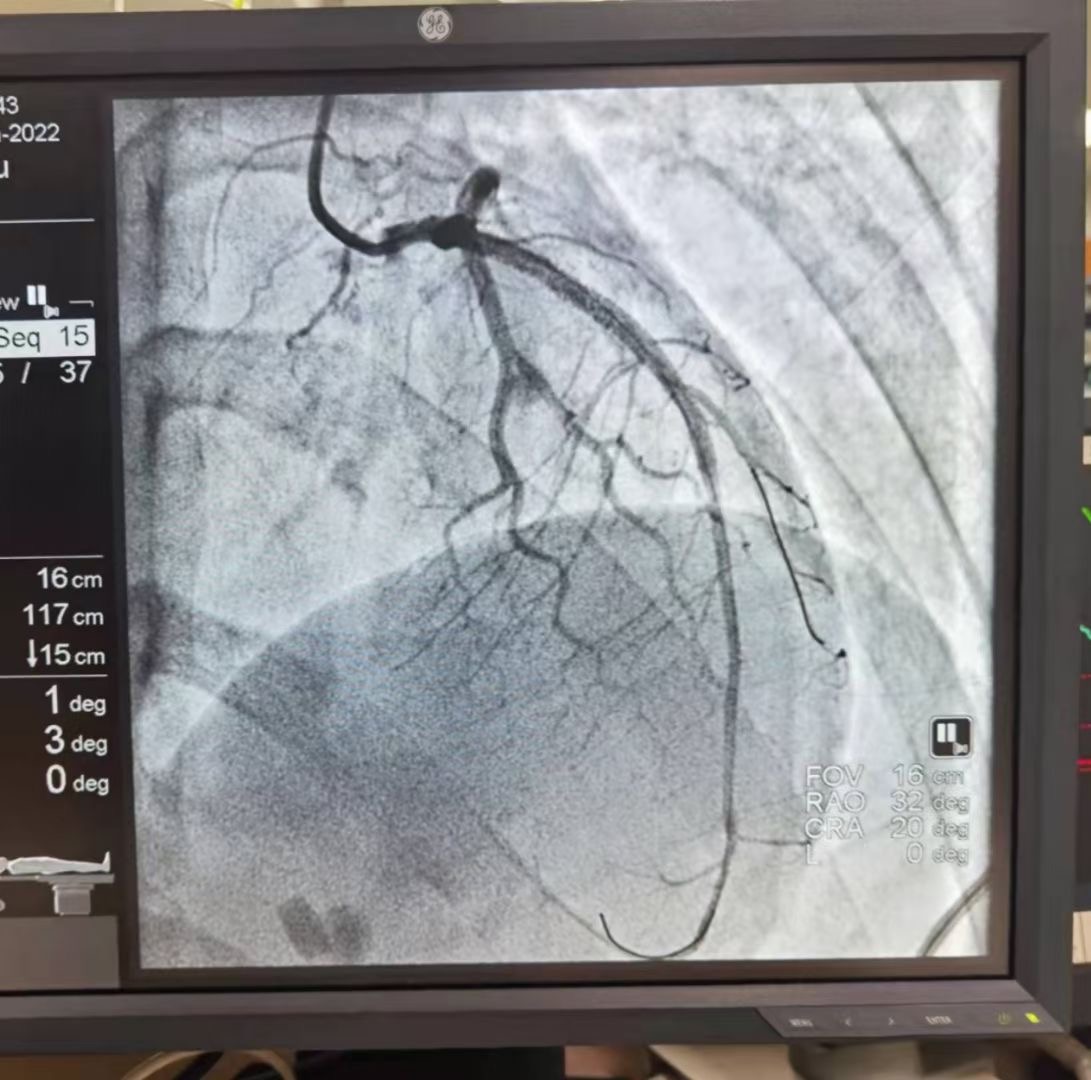

情况危急,急诊二部立即组织对小李的抢救,经绿色通道送至胸痛中心导管室,急诊行多根导管冠状动脉造影术加急诊经皮冠状动脉介入手术(PCI)、经皮冠状动脉内支架置入术(STENT),经过导管室的努力,凌晨两点多,手术顺利完成,小李被送往急诊监护病房继续治疗。